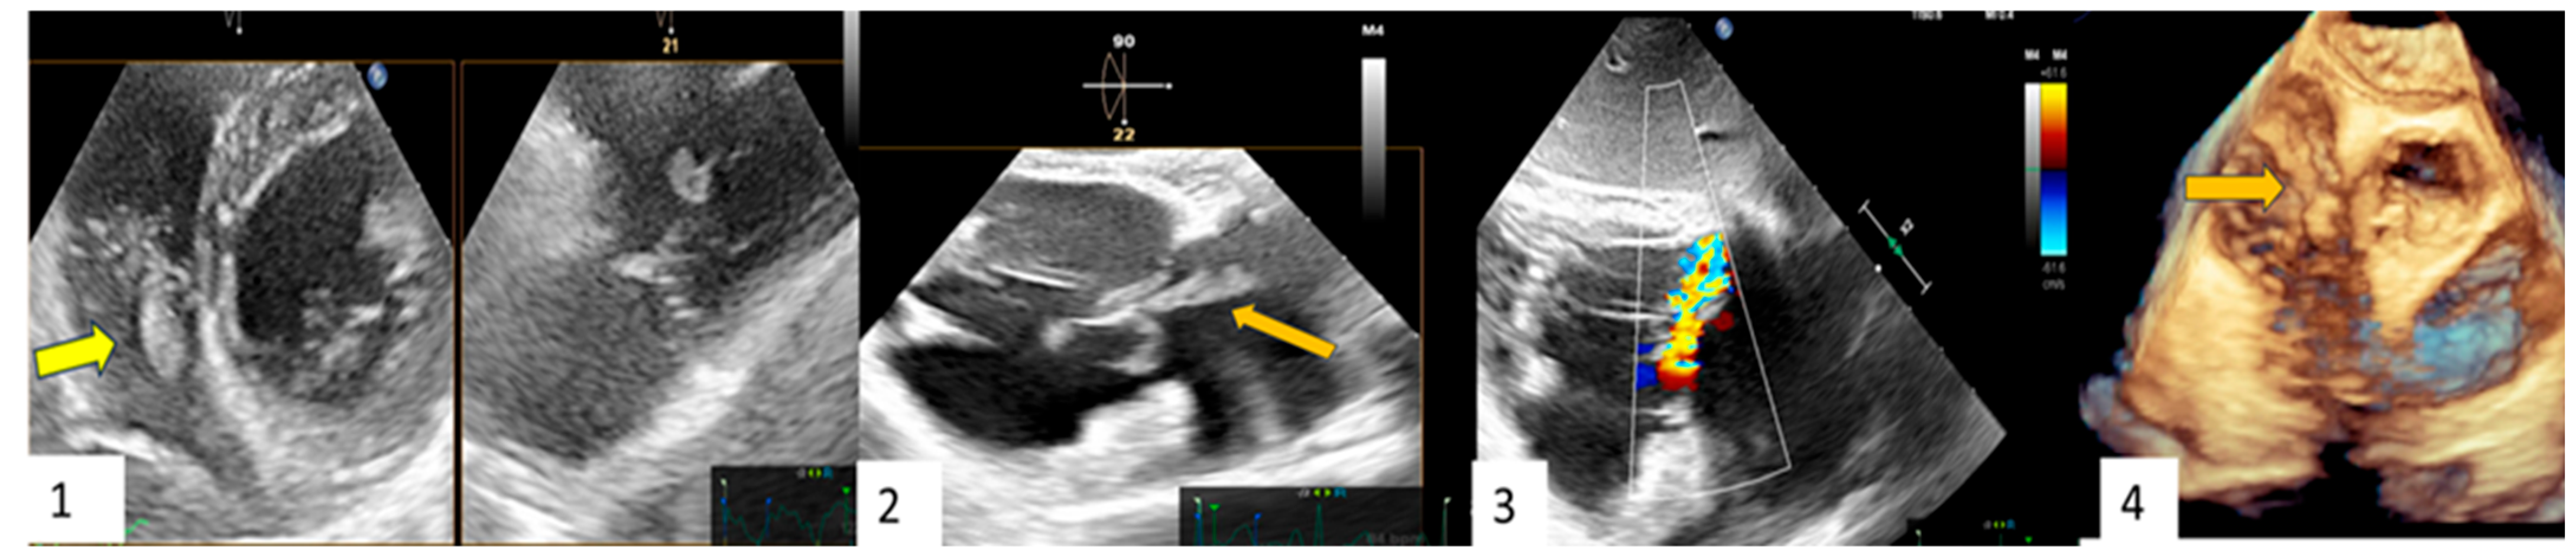

Clinical Case 4. Unexpected clinically silent IE recurrence. A 76-year-old man undergoing previous Bentall aortic surgery with a bioprosthetic valve. The patient remained asymptomatic for 6 years after surgery until the appearance of lumbar pain (subsequent diagnosis of spondylodiscitis at magnetic resonance imaging) without fever and Reactive C Protein increase. Due to Streptococcus Bovis bacteremia, the patient underwent TTE and TEE, showing mobile vegetation attached to the ventricular face of the aortic prosthetic leaflet. Following specific antibiotic therapy, TEE (1A) and CT scan (1B) showed a successful outcome with vegetation disappearance in the absence of clinical events related to a systemic embolization. In the absence of symptoms, to assess spondylodiscitis status, the patient underwent PET (2A–C), showing complete recovery from the spinal infection with concomitant imaging of abnormal FDGuptake involving the posterior side of the ascending aortic prosthesis and valvular prosthetic ring, suggesting a recurrence of bioprosthesis endocarditis with paraprosthetic ascending aortic abscess (red arrow). The findings were confirmed with subsequent CT (2D), TEE (2E,F) (yellow arrow), and surgical specimen (3). Blood cultures and histopathological examination were positive for Candida Albicans